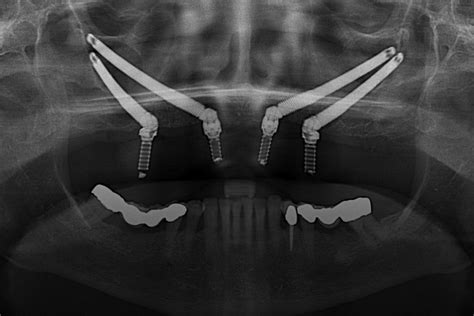

Existen varias técnicas para reemplazar toda la boca con implantes y el precio variará en función de la técnica utilizada. Las prótesis híbridas sobre implantes son una de las soluciones que tenemos cuando queremos reponer toda la boca con implantes. Los implantes cigomáticos son un tipo de implantes que se utilizan para pacientes que no tienen hueso.

Todas nuestras intervenciones de implantes dentales en Bilbao se realizan con cirugía guiada por ordenador, la cual, nos permite colocar de manera virtual los implantes. Realizamos un estudio radiográfico con un escáner oral, obteniendo una imagen que reconstruye en dos y tres dimensiones la boca del paciente, con la que podremos simular la operación y permitir la colocación de los implantes en la mejor posición para obtener una estética y funcionalidad perfectas.

Posteriormente con la imagen que nos ofrece el estudio radiográfico fabricamos las plantillas quirúrgicas que reproducen con exactitud la posición definitiva de los implantes dentales. Estas plantillas nos sirven de guía para intervenir en la encía sin necesidad de abrirla, indicándonos donde y hasta que profundidad máximo debemos perforar.